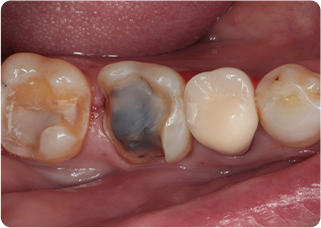

精密根管治療②

術前

術後

| 主訴 | 奥歯で噛むと痛い |

|---|---|

| 治療期間/回数 | 1ヵ月、3回 |

| 価格(税込) | 88,000円(税込) |

| リスク・副作用 | 病変再発、歯根破折の可能性 |

| ポイント | う蝕検知液を用い、むし歯の取り残しが無いようにし、ラバーダム防湿を行い、無菌的に根管治療を行った。根管充填材は、殺菌作用の強い保険適応外のMTAセメントを使用した。 |